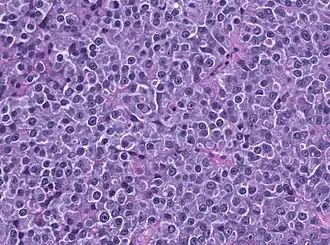

| Prolactinoma, HE. | |

Prolactinoma é um tumor benigno glandular (adenoma) da hipófise(glândula pituitária), que produz prolactina. É o tipo de tumor mais frequente na hipófise. mais frequente em mulheres em idade fértil. Causa infertilidade e disfunção sexual em homens e mulheres.[1]